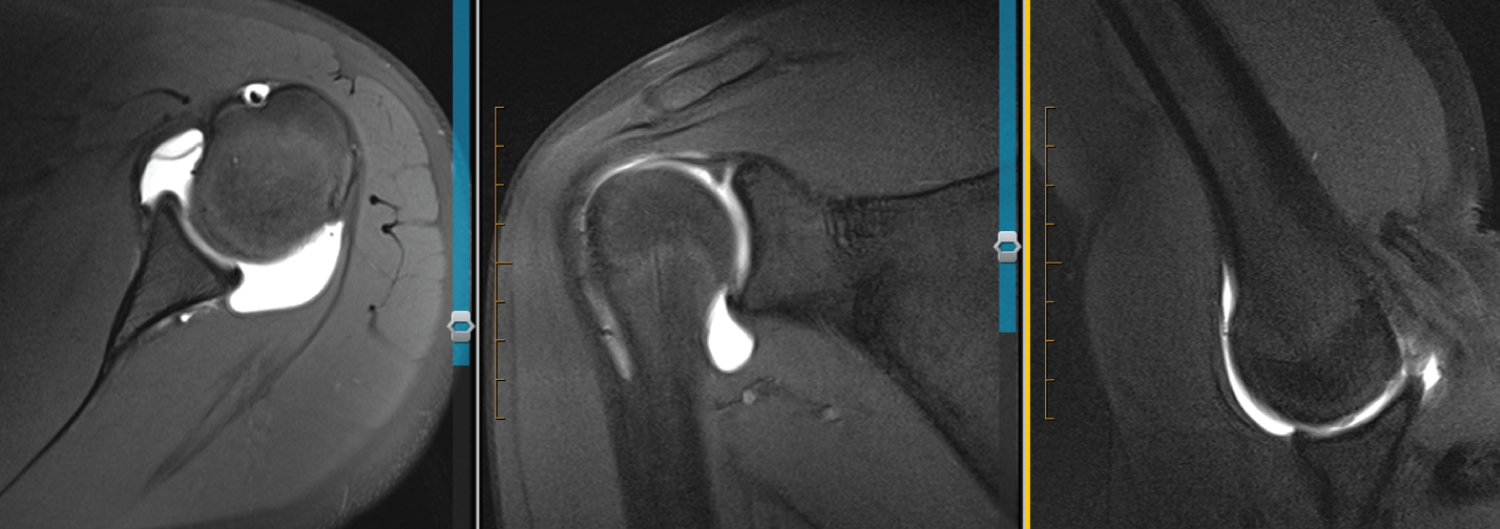

Figure 7: 17 F L MRA. Axial view shows blunted, rounded, and undefined anteroinferior labrum. There is some contrast dye present, likely injected into the IGHL. Which would show that it is still intact. ABER view confirms IGHL and labrum still intact. View Figure 7

Figure 8: 17 M L MRA. Axial view shows rounding and blunting of labrum with undefined features. ABER looks normal. View Figure 8

Figure 9: 15 F R MRA. Axial view shows blunted anteroinferior labrum with IGHL adjacent to it. Seems a little more defined compared with others. NO ABER views. View Figure 9